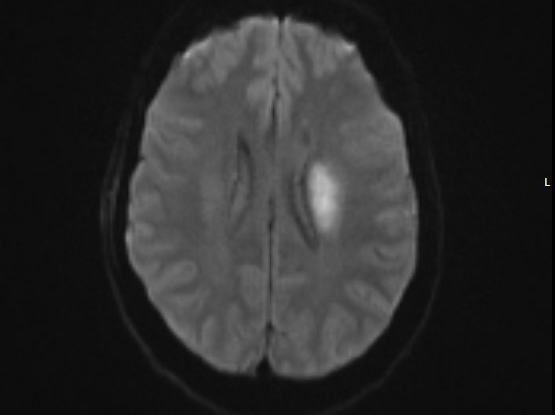

55-year-old female was admitted to our inpatient unit for neurological rehabilitation following stroke. Examination revealed right sided hemiparesis with power of 0/5 in upper limb and 2/5 in lower limb. Laboratory investigations were normal. Her lipid profile was raised. She also had an unremarkable 24-hour electrocardiogram and carotid Doppler. Brain Computed tomography and MRI scans showed left basal ganglia infarct. She was treated as an acute ischaemic stroke and commenced on rehabilitation. She was transferred to our unit to continue her neurological rehabilitation which was progressing slowly (Figure 1a –1c­­).

Figure 1a Magnetic resonance imaging showing left basal ganglia infarct.